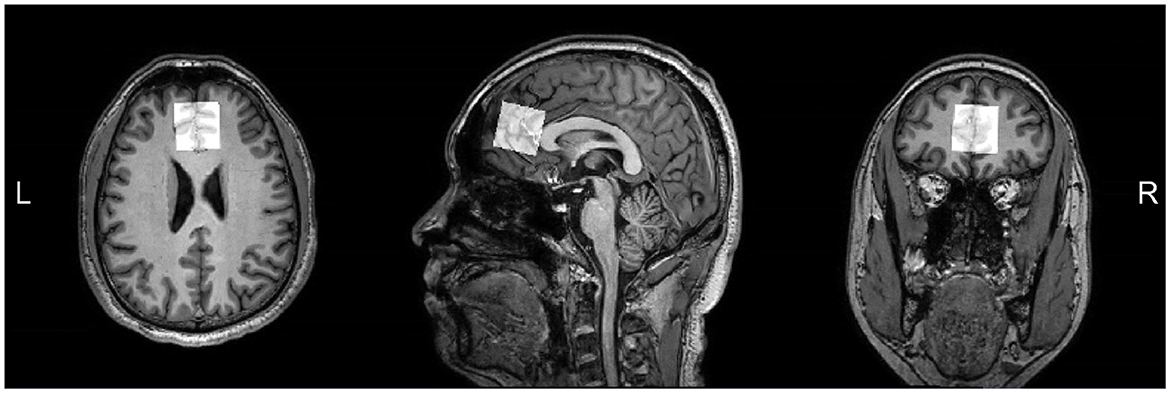

All subjects were scanned on a 3.0T MRI scanner (Ingenia CX, Philips Healthcare, Best, The Netherlands) equipped with a 32 channel heal coil in the Magnetic Resonance Department of the First Affiliated Hospital of Zhengzhou University. During the scan, subjects should stay awake and not fall asleep, and spongy pads were placed near their ears on both sides to stabilize their heads. In order to eliminate the interference of other organic brain lesions, we first collected some routine sequences for clinical diagnosis: including T1 weighted imaging (T1WI), T2 weighted imaging (T2WI), fluid-attenuated inversion recovery (FLAIR), and diffusion weighted imaging (DWI). For anatomical reference, a high-resolution 3D T1WI scan were carried out using the gradient echo sequence with following parameters: number of sagittal slices = 200, field of view (FOV) = 256 mm2, repetition time (TR) = 9 ms, echo time (TE) = 4 ms, slice thickness = 0.9 mm, and acquisition time = 3 min 26 s. The MEGA-PRESS sequence for GABA and Glx spectral editing was implemented with parameters as follows: TR = 2,000 ms; TE = 68 ms; number of signal averages (NSA) = 192 (both ON and OFF spectra were repeated by 96 times, totally 192 spectra); ON/OFF frequencies = 1.9/7.5 ppm; scan time = 6 min 30 s. The ON and OFF experiments of the MEGA-editing sequence were performed in an interleaved Fashion, and the VAPOR scheme was selected for water suppression (Tkáč et al., 1999). The acquisition of J-edited NAAG spectrum is also carried out using MEGA-PRESS sequence, and the parameters (Edden et al., 2007) was implemented as follows: TR = 2,000 ms; TE = 140 ms; NSA = 192; ON/OFF frequencies = 4.61/4.15 ppm; scan time = 6 min 30 s. The bandwidth of the editing pulses for both GABA/Glx and NAAG editing was 100 Hz. Unsuppressed water signals were recorded with 32 signal averages as an internal concentration reference. T1-weighted MPRAGE structure image provided reference for VOI localization in spectral scanning experiments, and the spectral data were obtained in a volume of 30 × 30 × 30 mm3 located in the frontal lobe of the brain (shown in Figure 1). FASTMAP shimming of the voxels was performed automatically before each acquisition, yielding water signal line widths of 6 to 10 Hz.

Figure 1. T1-weighted images showing MRS voxel placed in the mPFC on axial, sagittal, and coronal sections.